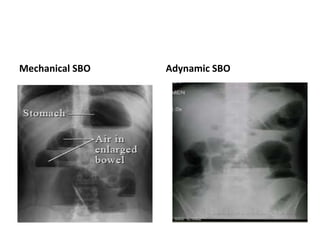

Small bowel obstruction

• In small bowel obstruction, dilated small bowel loops are seen

centrally on the radiograph.

• The valvulae conniventes should be visible across the whole width

of this dilated bowel.

• The dilated bowel diameter is greater than 3 cm but usually less

than 5 cm. There are likely to be several dilated bowel loops.

• The number of small bowel loops gives an indication of the level at

which the obstruction within the small bowel has occurred: the

higher the obstruction, the fewer the number of loops seen.

• No gas should be seen within the large bowel.

• An erect film tends to show multiple small Fluid levels, a

“stepladder” appearance.

Mechanical SBO Adynamic SBO